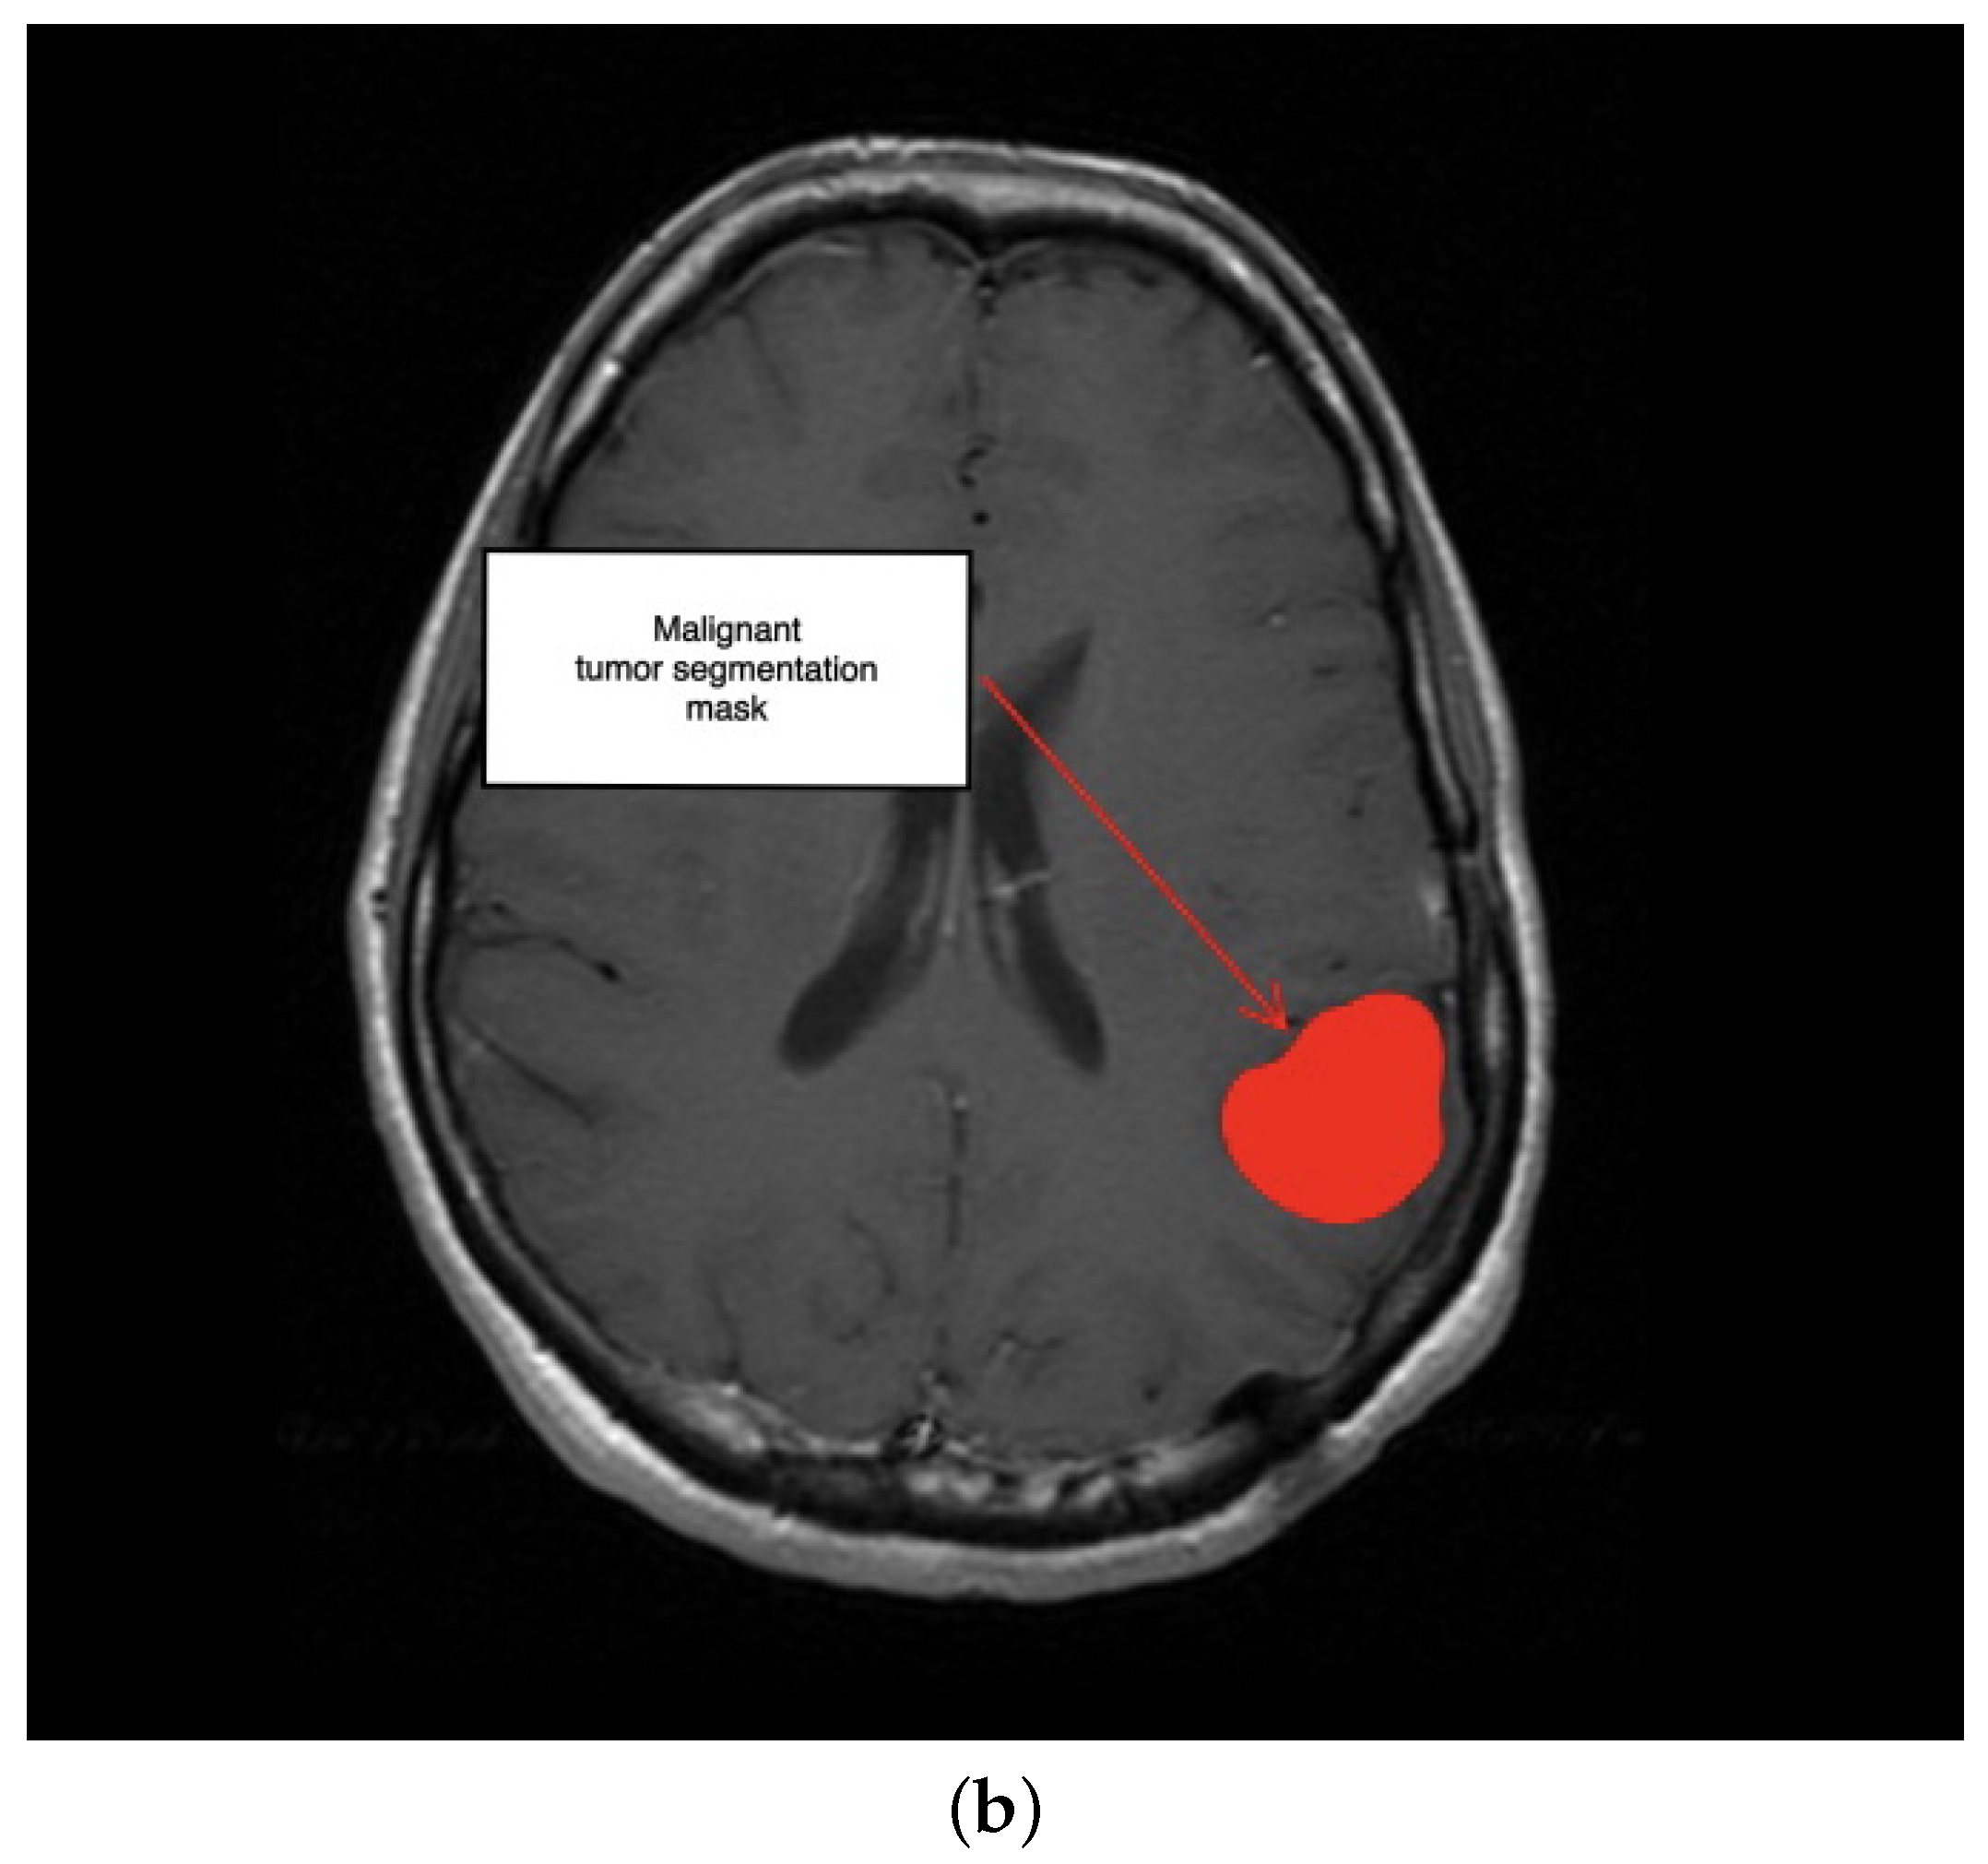

2. Description of the Methodology

3.1. First Scenario